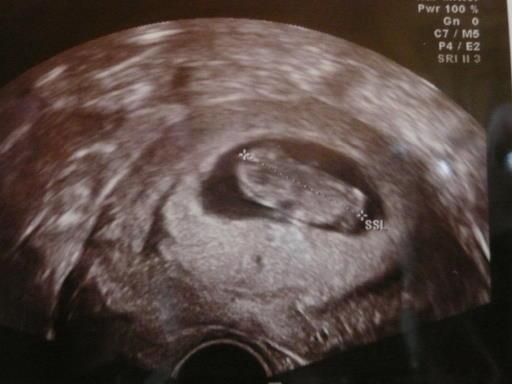

Und bin total happy. wurm idt 3,1 cm groß entspricht 10+0 obwohl ich erst 9+4 bin und hat mir zugewunken hier ein bild von meinem zwergi

Bild zu hatte grad vu - Forum für März - Mamis